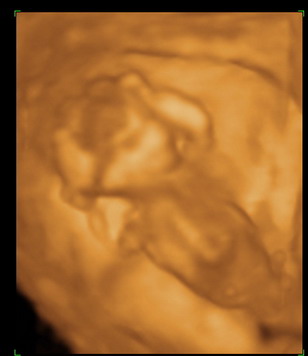

A héten előszedtem a babanaplót, amit még terhesen kezdtem és gyűjtögettem hozzá képeket, érdekes és vicces dolgot tapasztaltam.